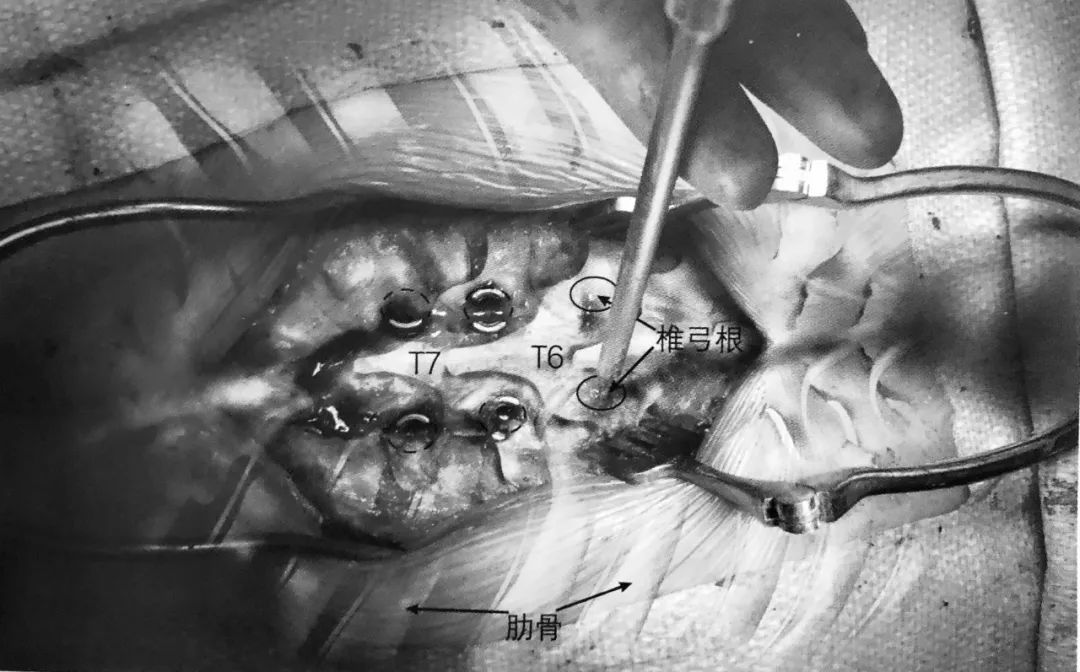

椎弓根钉侵犯内侧和下壁可能损伤神经根和脊髓

螺钉太长侵犯前方骨皮质可能导致血管或内脏损伤

椎弓根螺钉置钉位置不当可能引起螺钉拔出或固定失败